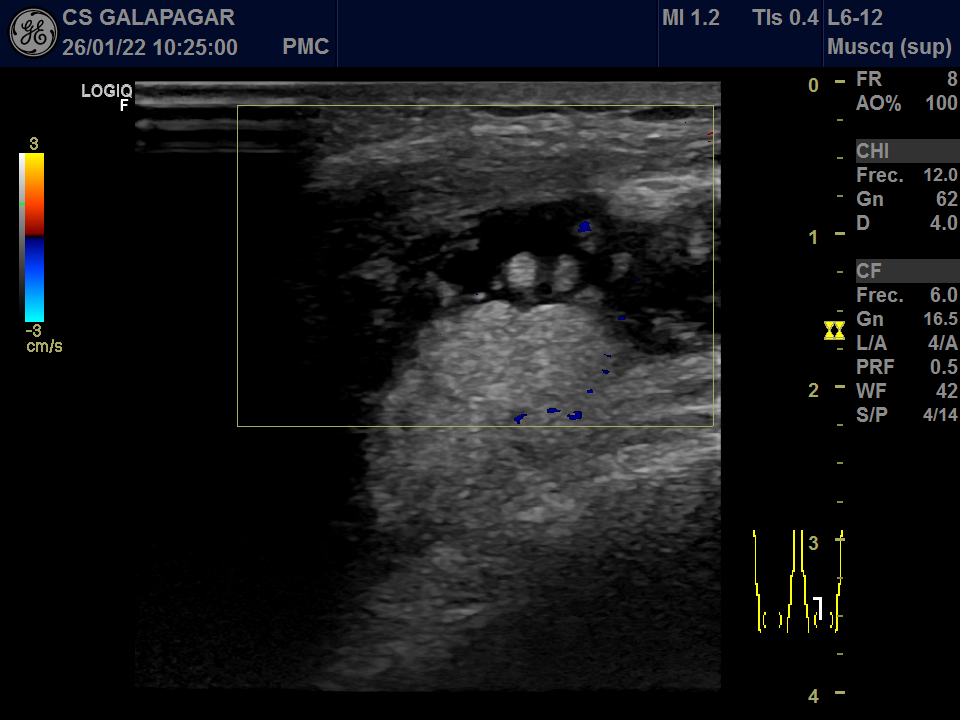

01/22: Abundante derrame en bursa con sinovitis muy proliferativa.